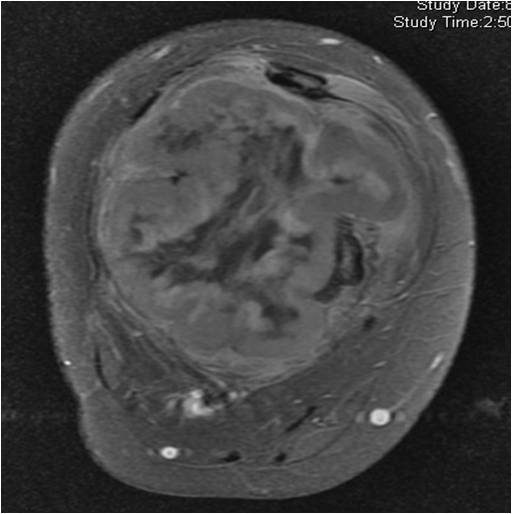

On radiographs, most MFHs of Bone are located in the metaphysis and present as purely osteolytic permeative lesions without a periosteal reaction and without mineralization (Fig. 1 &2). On MR images, MFH of Bone has ill-defined margins usually with cortical destruction of bone and extension into the soft tissues. It is usually hypo- or isointense to muscle on T1-weighted images (Fig. 3) and heterogeneous high intensity on T2-weighted images (Fig. 4-6).

Fig. 4-6: MRI Axial (Fig. 4) and (Fig. 5) T2 –weighted fat-suppressed images show a heterogeneous lesion in the distal femur. Axial T2- weighted fat suppress image (Fig. 6) demonstrates a heterogeneous lesion with hyperintense areas admixed with hypointense signal areas concordant with hemorrhage and necrosis. High grade sarcomas are commonly associated with hemorrhage and necrosis.